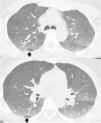

Expiratory CT scan is a complementary technique of inspiratory CT that provide valuable physiological information and may be more sensitive to detect air trapping than pul-monary function tests. It is useful in many obstructive airway diseases, including obliterative bronchiolitis, asthma, Swyer-James syndrome, tracheomalacia, hypersensitivity pneumonitis and sarcoidosis. In obliterative bronchiolitis, expiratory CT scan may be the only imaging technique that shows abnormalities in the early phase of disease. In order to obtain a good quality study, we should explain the procedure to the patient, use precise instructions and do some practice before image acquisition. Here we describe strategies to optimize the techni-que and propose an algorithm that help in interpretation of imaging findings in patients with obstructive airway disease.